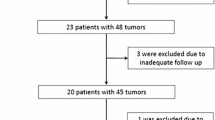

The study was conducted in accordance with the guidelines of the local institutional review board. Written informed consent was obtained from all subjects. Since 2000, 89 patients with CRC and liver metastasis received image-guided percutaneous hepatic RF ablation therapy in our institution. 26 of them (18 men, 8 women, mean age: 62.9 ± 8.8 years, age range: 39–82 years) were treated under CT-guidance for 38 hepatic metastases. In 21 patients one single lesion was treated, in 4 patients 2 lesions were treated, in one patient 4 lesions were treated, and in one patient 5 lesions either in one or in multiple sessions were treated. In accordance with current practice, results of follow-up imaging, histopathology, and clinical and laboratory parameters including tumor markers were used to verify the absence/presence of residual or recurrent viable tumor, so-called “local tumor progression” as defined in terminology and reporting criteria established by the international working group of image-guided tumor ablation [16]. The mean general observation period including all other available imaging modalities as well as clinical follow-up ranged between 63 and 1203 days (mean: 499 ± 393 days).